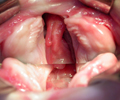

Las técnicas quirúrgicas que aplicamos a los niños fisurados son las más avanzadas y aceptadas internacionalmente, con resultados de alta calidad. En su primer mes de vida y sólamente sí lo precisa, le colocamos en su boquita ORTOPEDIA PREQUIRÚRGICA. A los 3 meses operamos el labio, la nariz y la encía. A los 12 meses se interviene la fisura palatina. Al año el niño está definitivamente corregido.

El tratamiento de los niños con fisura facial debe ser integral y realizado por un equipo multidisciplinar, para así obtener los mejores resultados funcionales y estéticos.